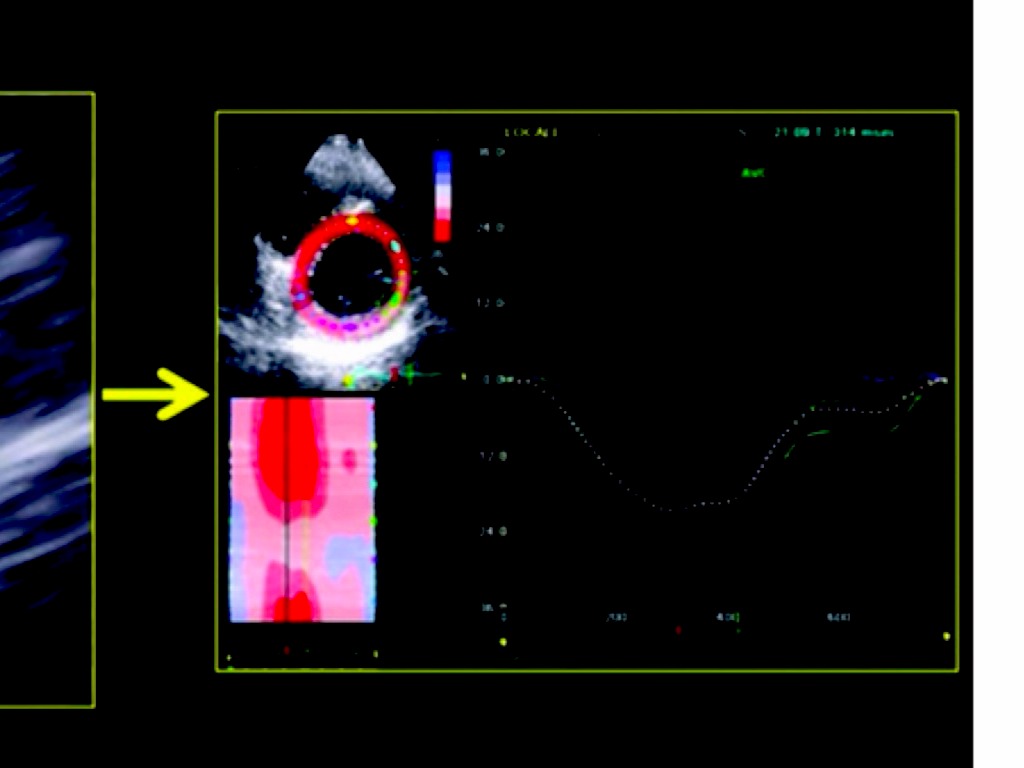

APLICAÇÃO DO STRAIN E STRAIN RATE NO DIAGNÓSTICO E MANEJO DA MIOCARDIOPATIA ISQUÊMICA

Georgia Rocha - MTDIC 4ª EDIÇÃO - Fev. 2014